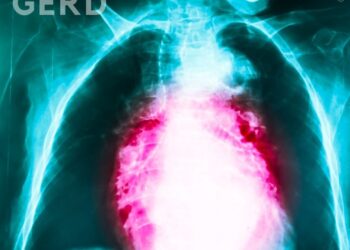

Read moreby Art Solbrig February 01, 2021 GERD, or Gastroesophageal Reflux Disease, happens when the sphincter at the esophagus base that...